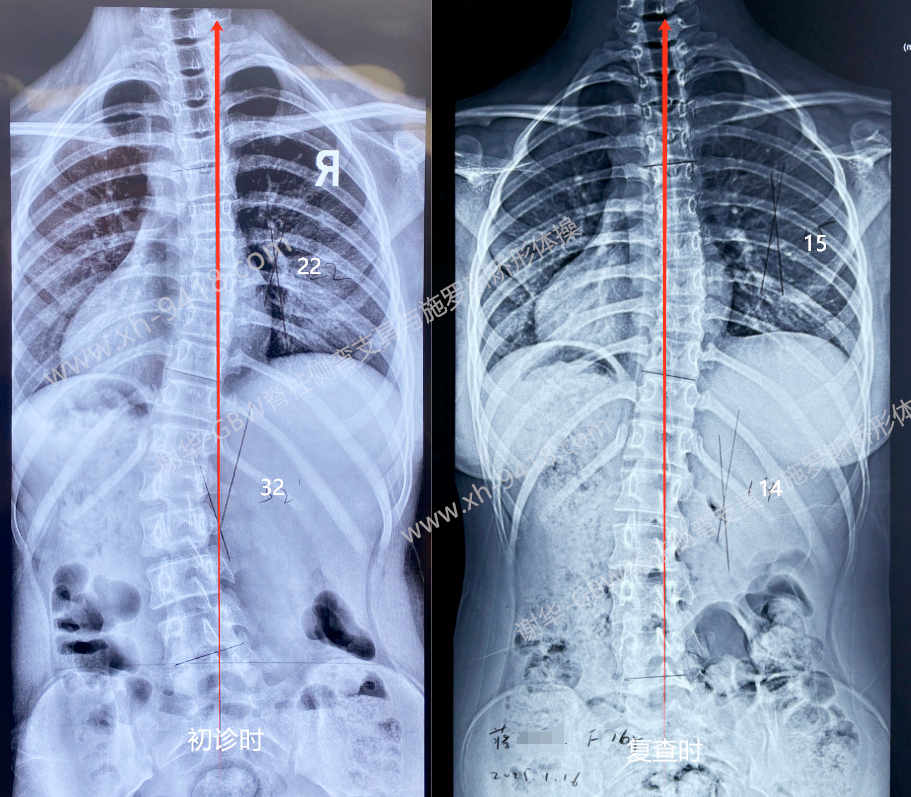

蒋X,女,13岁时发现脊柱侧弯。初诊时为典型的“S形”曲线,Cobb角为胸弯22°,腰弯32°,剃刀背分别为胸7°、腰8°;当时Risser征为2级,且初潮仅半年,根据青春期女孩生长发育规律,未来存在明显加重的风险。建议家长为孩子配置GBW型支具,并结合施罗斯体系的体操训练进行系统矫正。

经过2年多的坚持佩戴与训练,孩子的弯度逐渐得到控制和改善。近日在16岁复查时,胸弯为15°,腰弯14°,整体保持为轻度的对称性S形曲线。体表外观也明显改善,站立位时躯干对称性良好,剃刀背降至5°以下,回到正常范围。

初诊和复查时度数改善情况